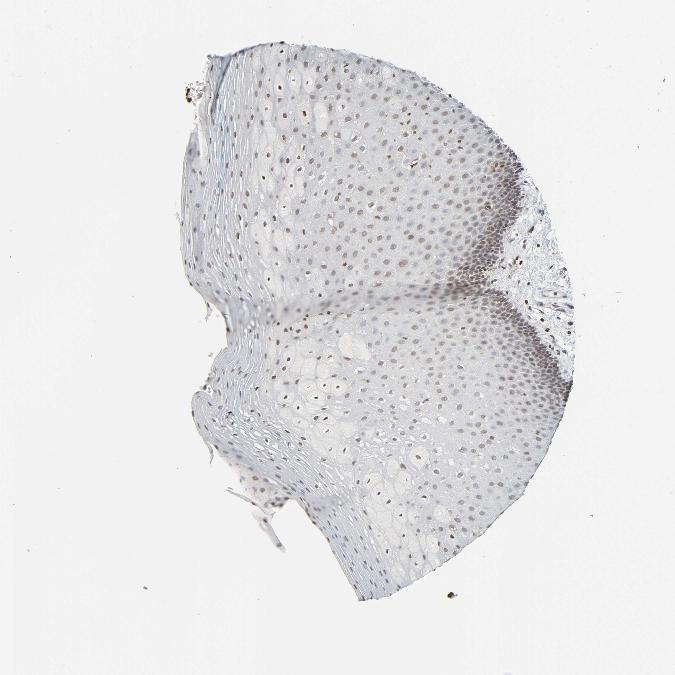

TISSUE PRIMARY DATA ORAL MUCOSA Show tissue menu

ORAL MUCOSA - Antibody stainingi

Antibody staining in the annotated cell types in the current human tissue is reported as not detected, low, medium, or high, based on conventional immunohistochemistry profiling in selected tissues. This score is based on the combination of the staining intensity and fraction of stained cells.

Each image is clickable and will lead to virtual microscopy that enables deeper exploration of all samples and also displays staining intensity scores, fraction scores and subcellular localization as well as patient and tissue information for each sample.

Antibody HPA015270Antibody CAB004038

Squamous epithelial cells LowLow